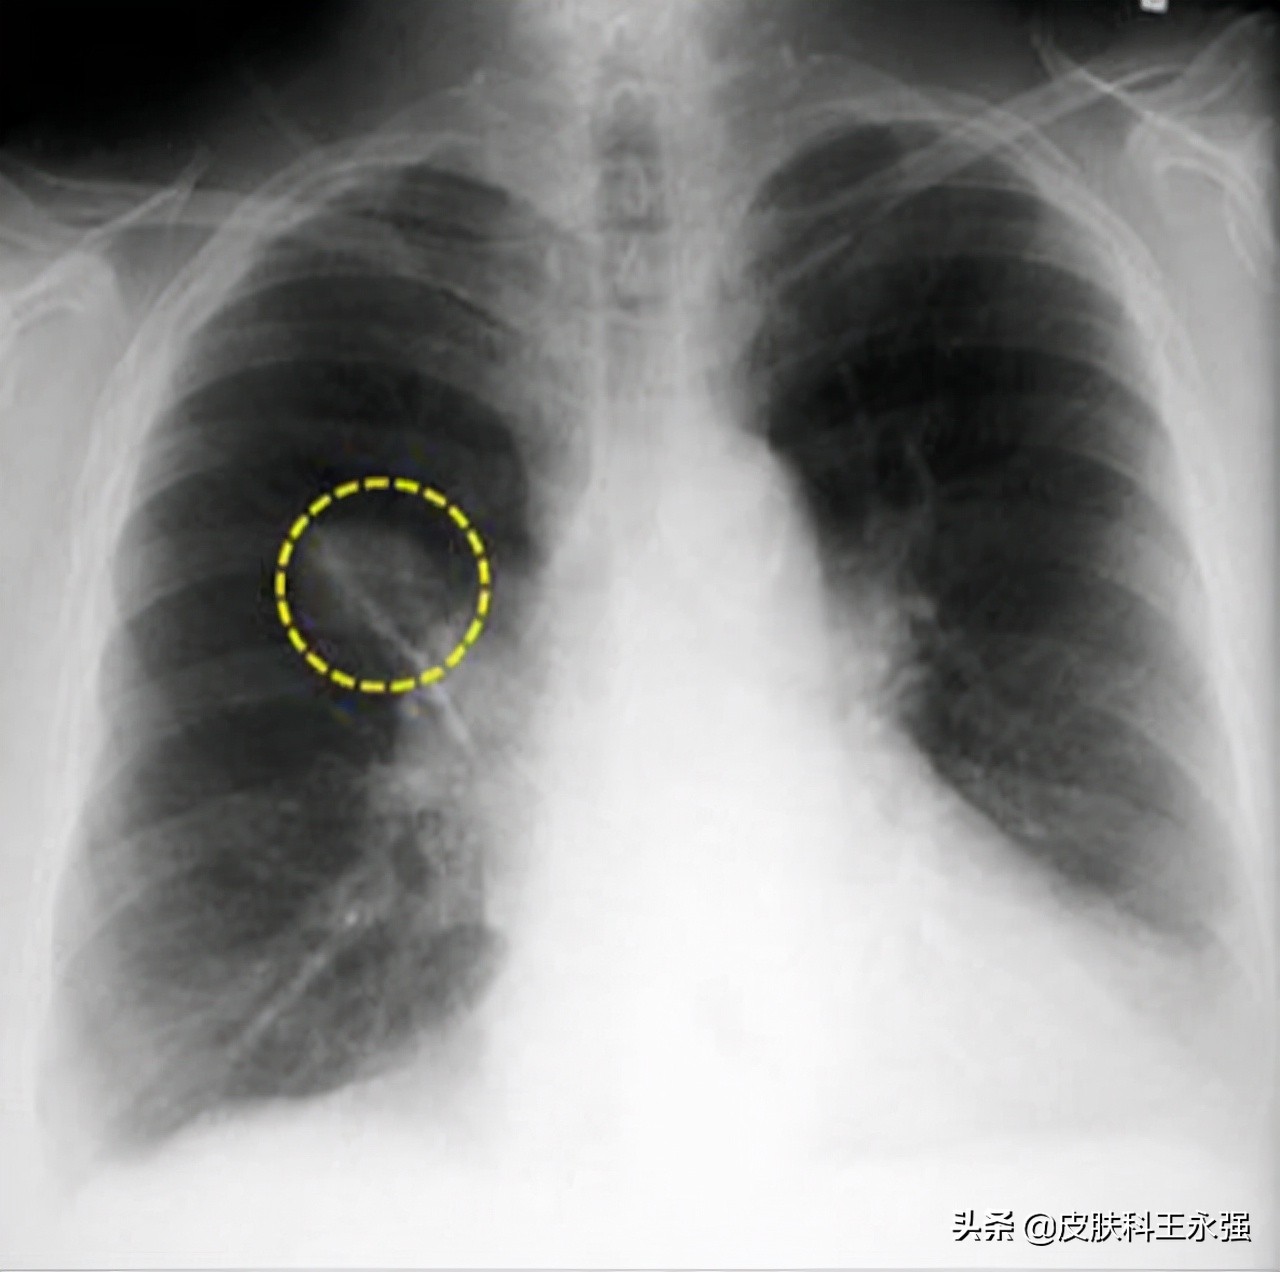

肺结节,一般指直径不超过3.0cm的,类圆形或者是不规则形状的病灶,可以是单发,也可以是多个结节。根据结节的大小,5-10毫米的又被细分为肺小结节,而小于5毫米的叫做肺微小结节。直径超过3.0cm的,就称之为肺部肿块。

肺结节又分为实性结节和磨玻璃结节,磨玻璃结节包括纯磨玻璃结节和混合磨玻璃结节。其中,不透明的实性结节和半透明的混合磨玻璃结节恶性程度较高,需要尽早就医。纯磨玻璃结节虽然生长缓慢,风险较小,但也要注意,以免发展为混合磨玻璃结节。

肺结节,同样有良恶之分。但90%以上都是良性的。直径小于8毫米的大多为良性,20毫米以上的有半数概率是恶性的。而对于良性的肺结节也不能够掉以轻心,需要定期检查,避免不能及时发现结节异常的可能情况而延误病情。直径越大的结节发生异常,恶变的概率就会越大。同时,如果你存在长期吸烟、饮酒,或者肥胖等高危因素的话,癌变的风险就会增加,要及时预防感染。